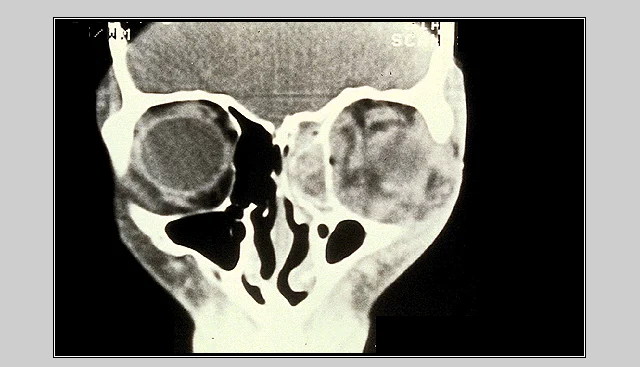

Management of Orbital Cellulitis

- CT Scan.